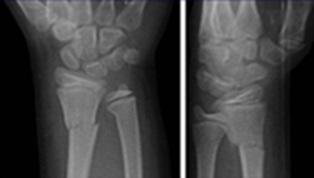

Fractura de Colles

Llamada también Fractura de Pouteau-Colles: es una lesión extraarticular de la metáfisis del radio (clasificación de Frykman I). Es la fractura más frecuente del miembro superior (ENAM 2013-A). El mecanismo de lesión es por caída sobre la palma de la mano (mano en dorsiflexión). Es común en ancianos con osteoporosis.

Clínica: Deformación de la muñeca de la mano con desplazamiento dorsal y radial, los cuales generan los signos del “dorso de tenedor” y el signo de la “bayoneta”, respectivamente. Asimismo, se describe el signo de Laugier, en la cual el estiloides radial se ubica en la misma línea que el estiloides cubital. La dorsiflexión, así como el desplazamiento del fragmento roto pueden comprometer el nervio mediano.

Recuerda

La inmovilización del miembro superior, luego de una fractura de Colles, es aproximadamente 6 semanas, tiempo luego del cual se ha formado un callo óseo apropiado.

Tratamiento: En casos de lesiones no complicadas, el manejo es ortopédico con reducción ventral y cubital. La inmovilización inicial se recomienda con yeso braquipalmar por tres semanas, seguida de un yeso antebraquiopalmar por tres semanas más. Aproximadamente 6 semanas de inmovilización en pacientes sin osteoporosis.

Fractura de Goyrand - Smith

También corresponde a una lesión de la metáfisis del radio. Sin embargo, el mecanismo es por caída sobre el dorso de la mano (o hiperflexión), con la respectiva desviación ventral o palmar de la mano con el fragmento fracturado. (Colles invertido).

Clínica: Deformación de la muñeca de la mano, con desviación ventral (signo de la “pala de jardinero”).

Tratamiento: el manejo es quirúrgico.